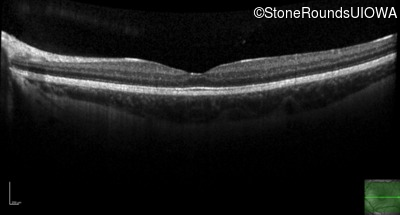

Optical Coherence Tomography - Right - 20/50

Exemplar / OCT Stack